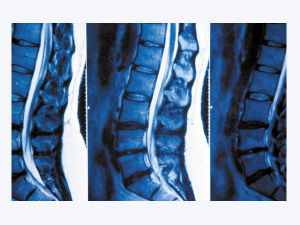

肌肉勞損也叫肌筋膜炎、腰肌勞損、腰肌筋膜炎。實質是一種無菌性炎症,主要表現為患處疼痛,壓痛和功能障礙.勞損好發於支配多動或負重關節的肌肉或維繫這些關節的韌帶,尤其是肌肉或韌帶在骨質上的附著點.長期,經常地重複某一特定的動作是造成超負荷使用的常見原因.西安治療腰肌勞損醫院 http://www.qzcgb.com/yaojilaosun/